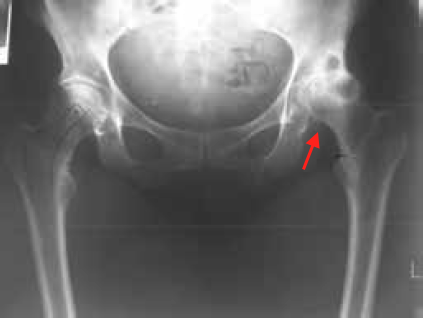

Hip Arthritis is a common condition that occurs when the cartilage which overlies the femur bone or lines the acetabulum bone wears out and exposes ‘bone on bone’ articulation. It is a progressive disorder, meaning it gradually worsens over time.

Osteoarthritis is the most common form, characterised by the breakdown of the joint’s cartilage. The next common form is rheumatoid arthritis, which is a chronic inflammatory disease of the joint and soft tissues.